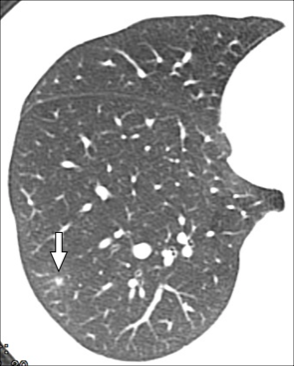

CT主要表现为三处非常细小的渗出(图1-3箭头所示):

图3

回到这个小护士病例,根据水痘表现,加上影像学表现为GGO、小结节周围GGO,应该比较符合的,可以临床诊断为水痘肺炎。但本病例仅发现3个小病灶,没有广泛累及,推测原因可能是先前可能接种过水痘疫苗,肺部累及较轻。

本例患者是因筛查新冠CT检查而意外发现的轻微的水痘肺炎,病程中并无明显咳嗽、气急与呼吸困难。当然此例水痘肺炎是建立在临床诊断基础之上,有必要进一步跟踪随访。